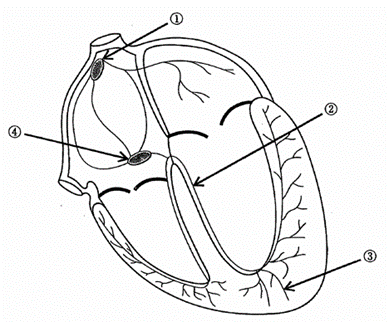

心臓の興奮伝導系を模式図に示す。一定のリズムで興奮し心房を収縮させるのはどれか。1つ選べ。

a. ①

b. ②

c. ③

d. ④

解答を見る

a